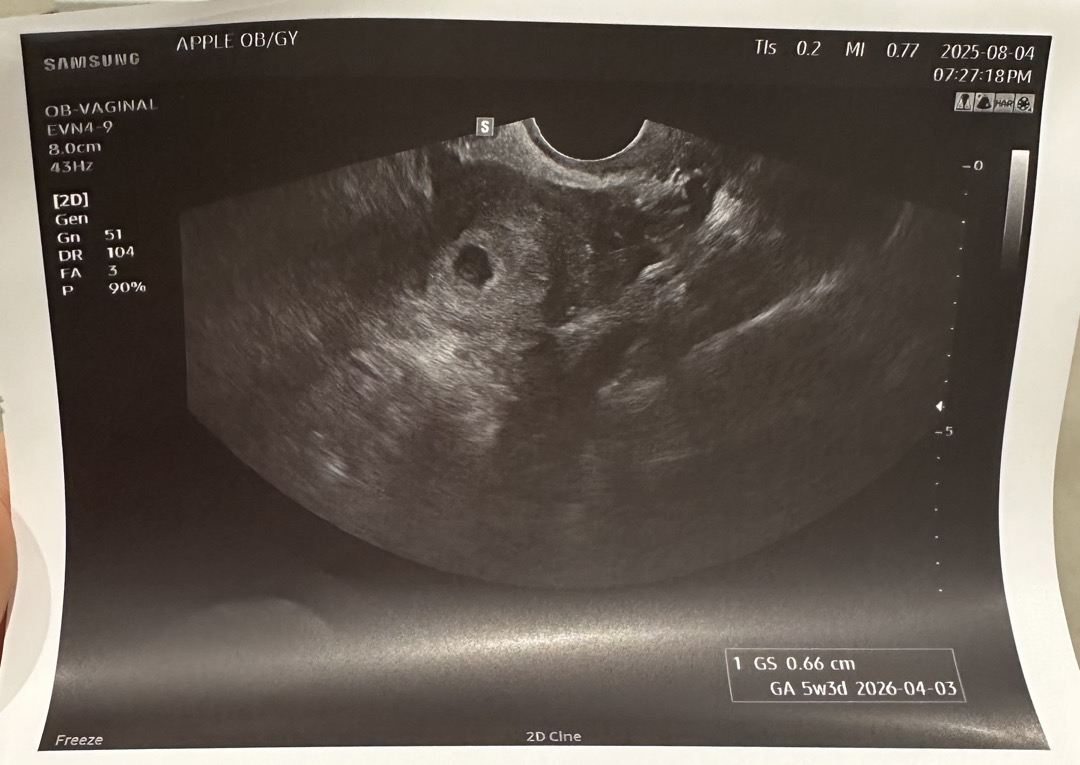

아기집 보고 왔어요..!! (Feat.희미한 난황..?)

동그랗게 뚝딱뚝딱 잘 지어놨더라구요🥹 아~주 자세히 보면 흰색 링? 반지모양같은게 보이는데 선생님도 난황같긴하다고 애매하지만 담에 더 선명히 보자고 ㅋㅋㅋ.. 매직아이일까요..?🥺